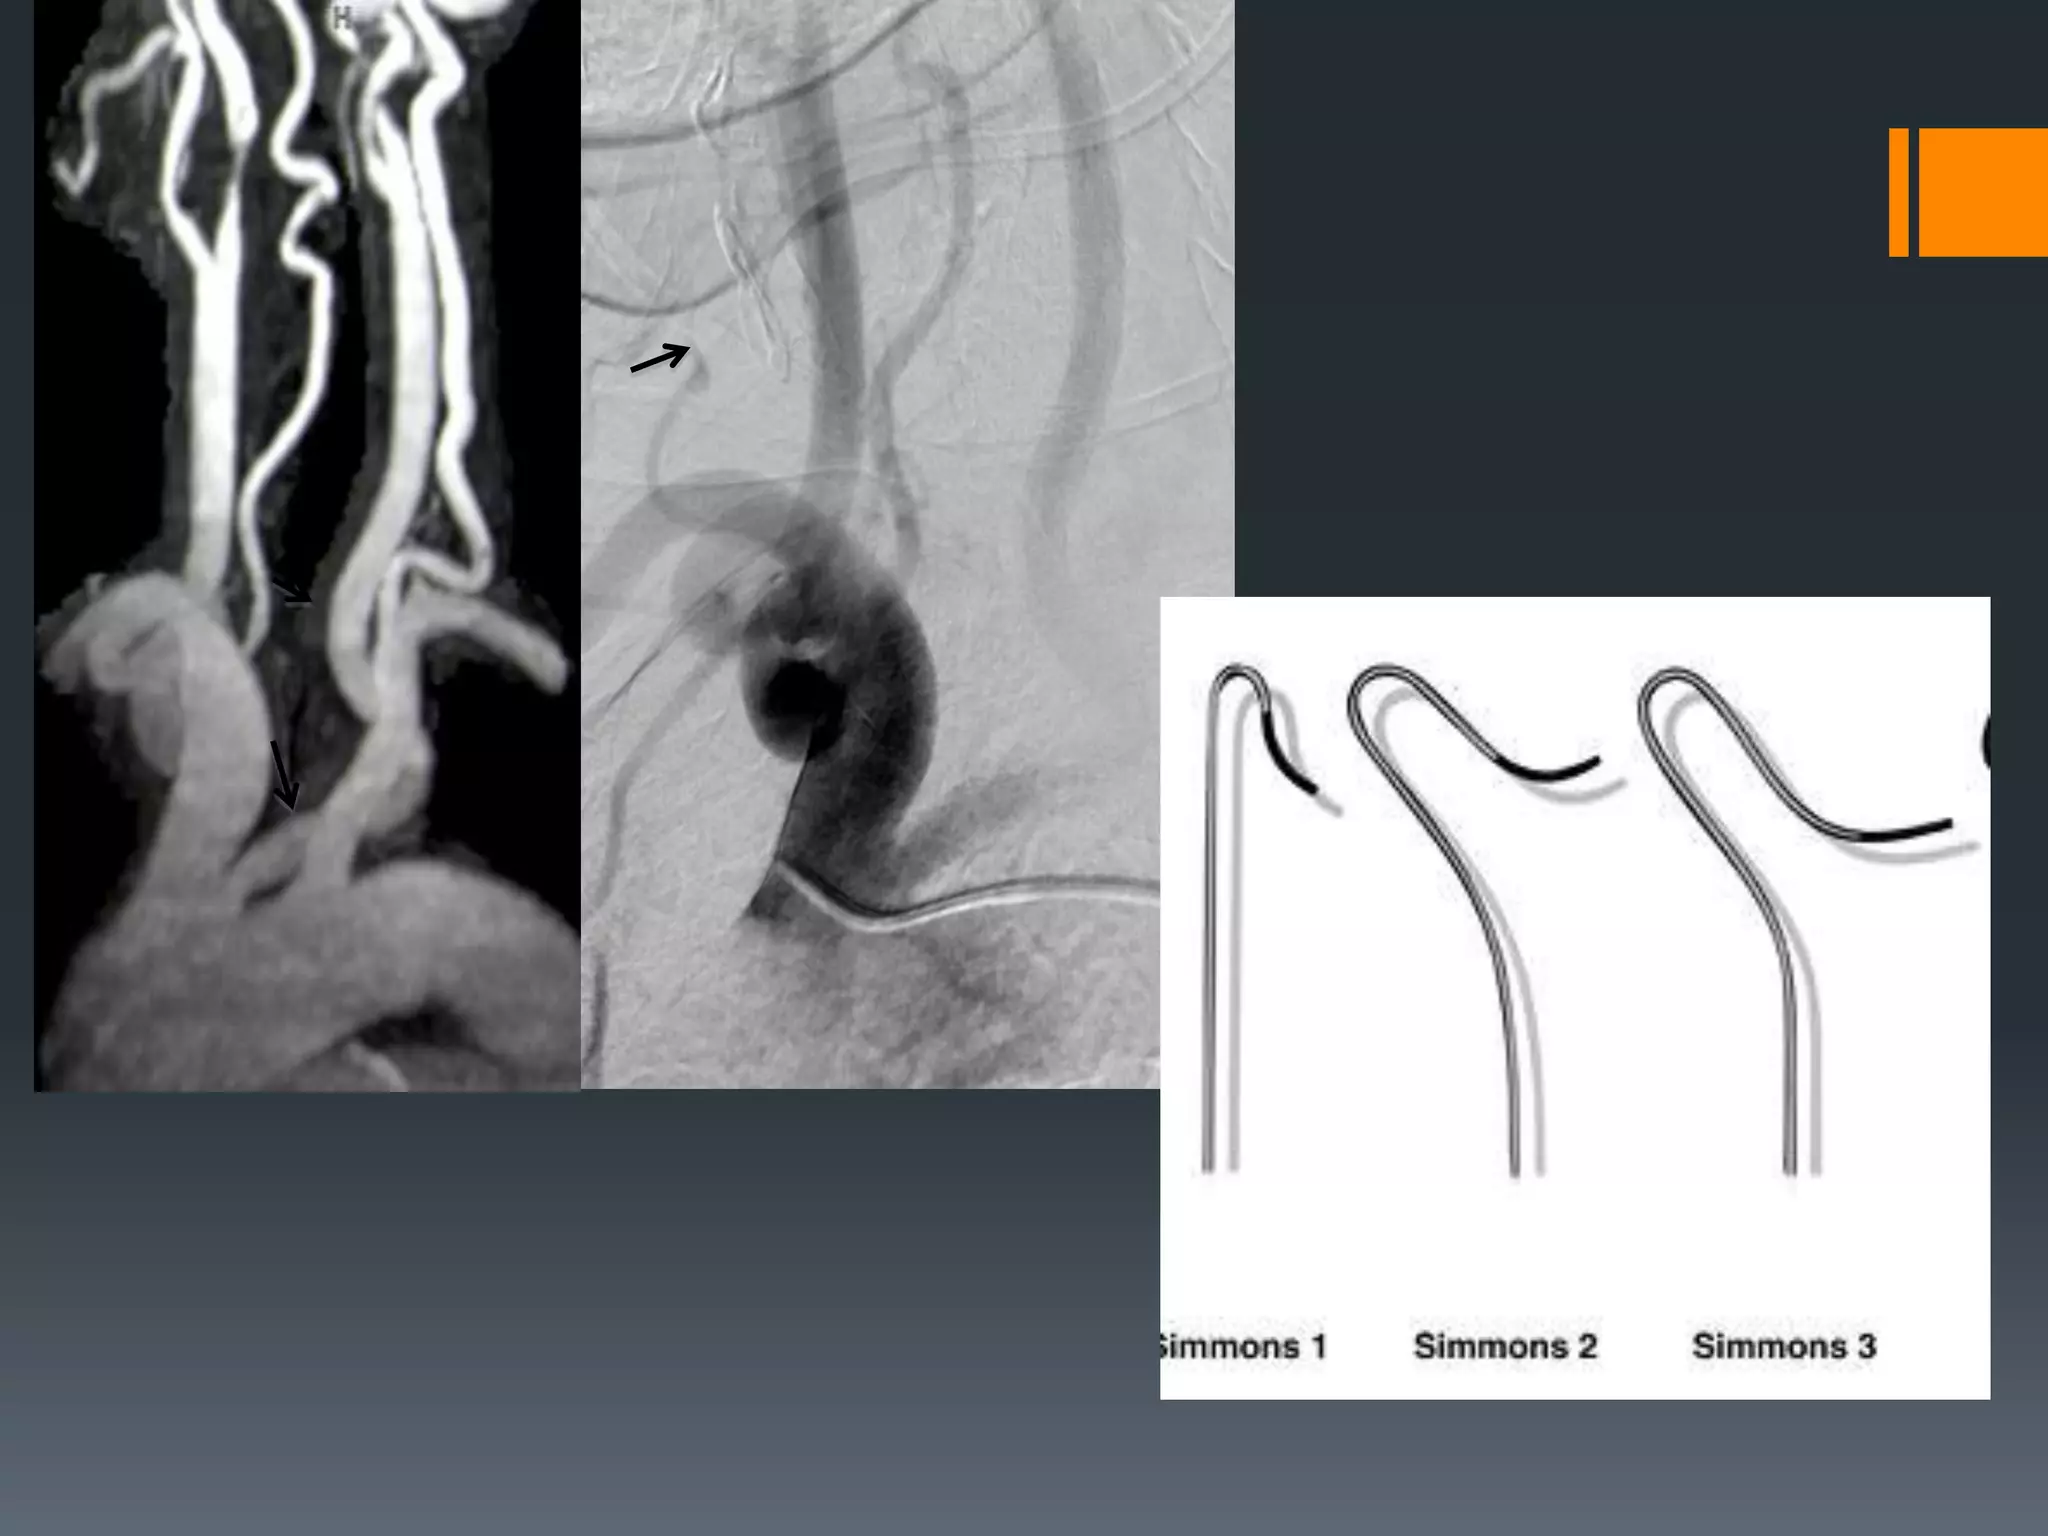

This document discusses tricks and techniques for difficult cannulations during neurointerventional procedures. It outlines strategies for accessing the aortic arch, internal carotid artery (ICA), and areas distal to aneurysms. Long sheaths, distal access catheters, and co-axial techniques are presented as options that have improved cannulation success. Guidance on sheath and catheter selection is provided for different vessel paths. The importance of catheter placement as high as possible in the ICA is emphasized. Reverse curve cannulations are also mentioned. Overall, the document stresses that careful cannulation is critical for procedural success and different strategies may be needed depending on the vessel target.